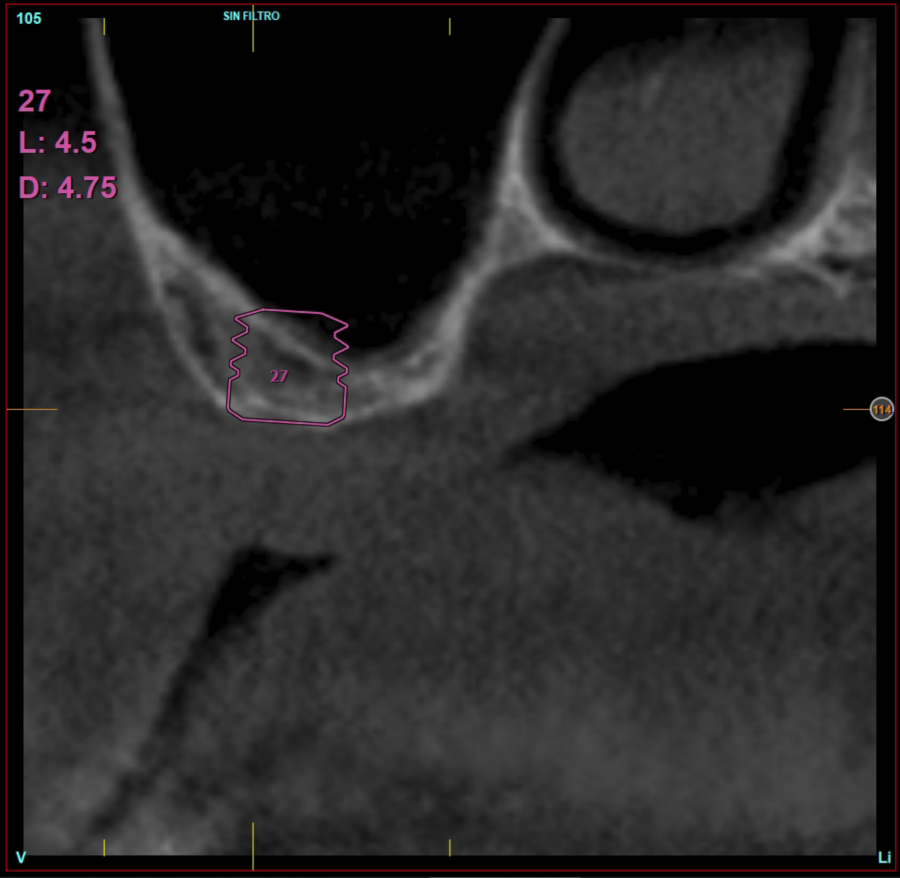

Ten patients who met the inclusion criteria were recruited, in which 20 implants were inserted. Three of them were women with an average age of 72 (+/- 6 years). None of the patients were smokers at the time of surgery and did not have any active periodontal disease. The majority of the implants diameter included in the study was 5 mm (60%), followed by 4.5, 5.5 and 4.75 mm (13.33% each). The predominant length was 5.5 mm (86.6% of the cases), with 13.4% of the remaining implants with a length of 4.5 mm. The most common positions were for the second molars (molars 27 and 17) representing 55% of the cases.

The mean height of the residual bone volume was 3.1 mm (+/- 0.3 mm with a range of 3-4 mm). In all cases, transcrestal sinus elevation was performed, with particulate autologous bone obtained from milling the neo alveolus generation zone for implant insertion, being the average of this elevation above the apex of the implant of 2.8 mm (+/- 0.99 range 1.9 -5 mm). In the CT control scan after one year of inserting the studied implants, the bone gain achieved was maintained, no decrease in the volume gained was observed, only three cases showed a decrease of between 0.4 and 0.5 mm of the initial volume at the end (Table).

Figures 2-19 show one of the cases included in the study.